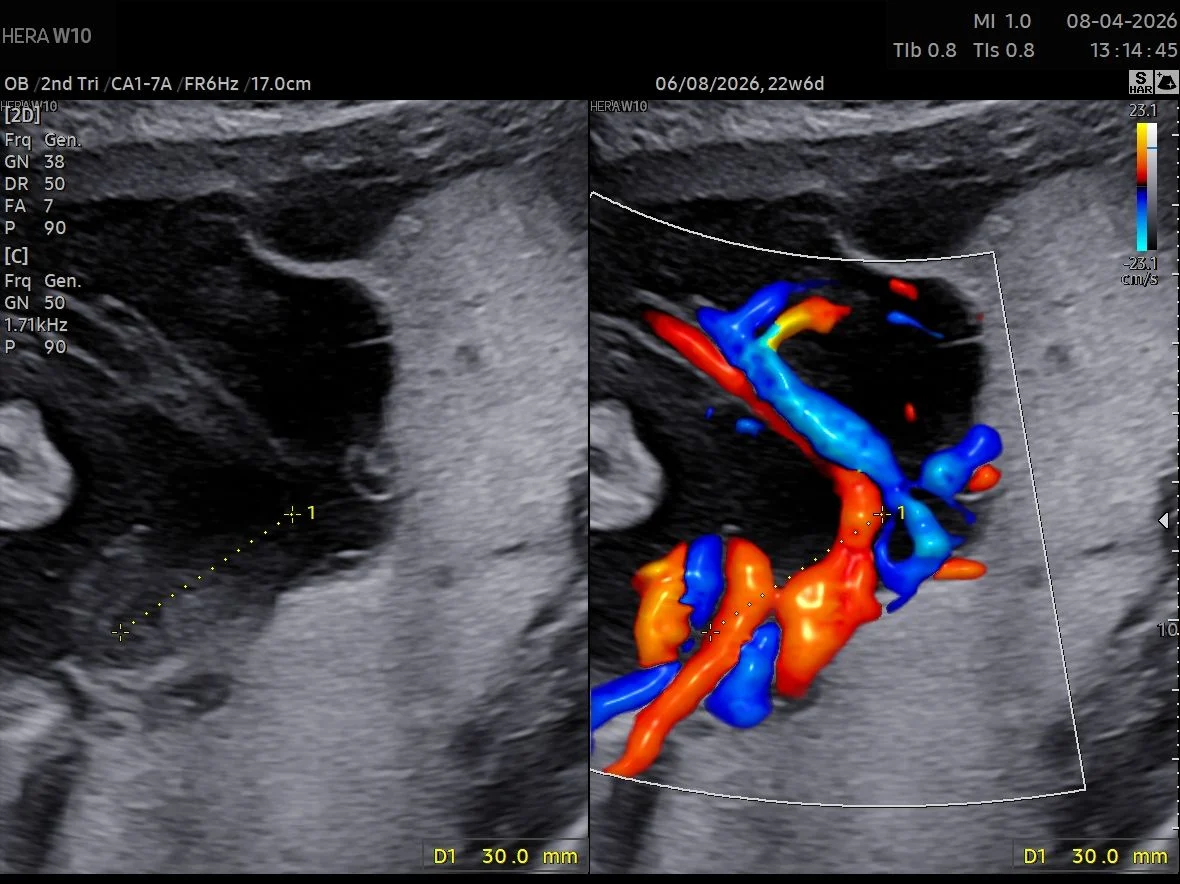

“Proximal cord insertion in MC twins

Proximal cord insertion (PCI) in Monochorionic twins is defined as cord to cord distance ≤ 4cm. It occurs in approximately 3-5% of MC pregnancies. it’s more common in MCMA twins.

Below is a a case of MCMA twins with PCI. Note also the large AA anastomoses between both cords with characteristic bidirectional blood flow.”